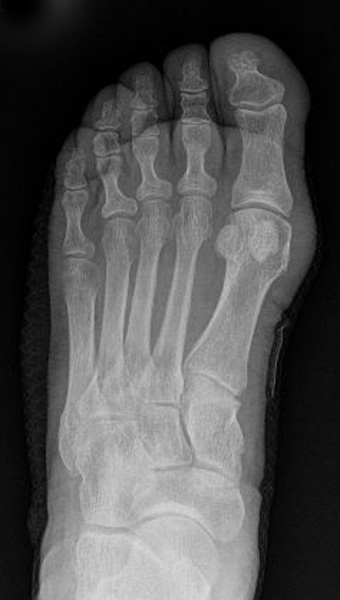

Abb. 12a: Typ III Deformität präoperativ im belasteten dp Röntgenbild.

Abb. 12b: Dorsoplantare Röntgenkontrolle nach medial schließender Osteotomie mit Schraubenosteosynthese.

Abb. 12c: Schrägaufnahme nach medial schließender Osteotomie mit Schraubenosteosynthese.